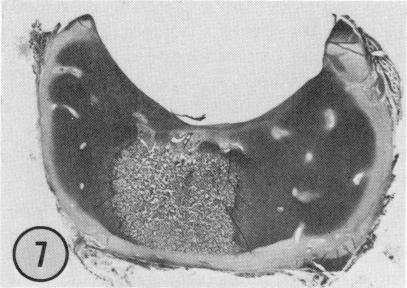

Seventy-four acetabula from a total of 140 normal human fetuses, obtained from abortions and deaths in the prenatal period, were used. The fetuses ranged from 9.1 to 40 cm in crown-rump length and are believed to be between 12 weeks and term. Acetabula were decalcified embedded in paraffin or celloidin, sectioned, and stained using conventional histologic techniques. Sections from the superior one-quarter of the acetabulum were examined for the initial appearance and later spread of osseous tissue. Throughout the fetal period bone was present only in the floor of the acetabulum and did not extend into the socket walls. Ossification was detected initially more posteriorly in the socket floor, and at all ages, ossification was more prominent on the ischial side of the socket. Despite the lack of osseous tissue a well-formed hyaline cartilage socket was present. The fetal labrum was composed of fibrous tissue with the density of fibers increasing with age. Typical-appearing chondrocytes were detected at only the inner articular margin of the labrum. Contributing from one-fifth to one-half of the socket depth, the labrum may play a greater role in containing the femoral head at birth than it does in the mature joint. In seven acetabula, from joints that were neither subluxated nor dislocated, an area of areolar tissue with capillaries was detected at the hyaline cartilage-labrum junction. Such defects may weaken the labrum and contribute to neonatal hip instability.

使用了从140例正常人类胎儿中获取的74个髋臼,这些胎儿是在产前因流产和死亡获得的。胎儿的顶臀长度在9.1至40厘米之间,据信处于12周龄至足月之间。髋臼经脱钙后包埋于石蜡或火棉胶中,切片,并采用传统组织学技术染色。检查髋臼上四分之一部分的切片,观察骨组织的初始出现情况及后续扩展情况。在整个胎儿期,骨仅存在于髋臼底部,未延伸至髋臼壁。骨化最初在髋臼底部更靠后的位置被检测到,并且在所有年龄段,髋臼坐骨侧的骨化更为明显。尽管缺乏骨组织,但仍存在一个发育良好的透明软骨髋臼。胎儿髋臼唇由纤维组织组成,纤维密度随年龄增加。仅在髋臼唇的内关节边缘检测到典型的软骨细胞。髋臼唇占髋臼深度的五分之一至二分之一,在出生时其在容纳股骨头方面可能比在成熟关节中发挥更大作用。在7个既未半脱位也未脱位的关节的髋臼中,在透明软骨 - 髋臼唇交界处检测到一个含有毛细血管的疏松组织区域。此类缺陷可能会削弱髋臼唇并导致新生儿髋关节不稳定。